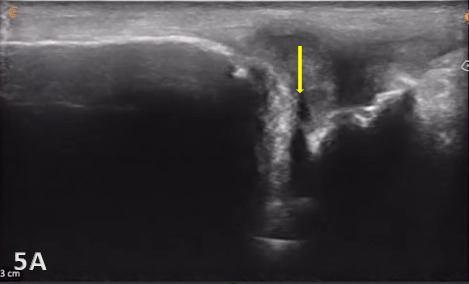

Normal TFCC appears as a thin, continuous, triangular band of homogeneous echogenicity extending from the distal ulna toward the ulnar carpal bones. The margins are smooth and well defined, without fiber disruption or adjacent fluid collection. No abnormal gapping is observed at the ulnocarpal interface, and the surrounding joint recess remains collapsed in the absence of effusion.

Direct ultrasound findings of TFCC injury include:

Hypoechoic or anechoic cleft seen within the normal fibrillar pattern of a normal TFCC.

Irregular or disrupted margins of the articular disk.

Thinning or fissuring of the TFCC indicates a partial-thickness tear.

Abnormal thickness of the TFCC, such as thinning (degeneration) or thickening (edema or chronic overuse), may be seen as pathology.

A complete disruption of the continuity of fibers of ligaments or the disk with fluid extending into the joint would indicate a complete full-thickness tear of the TFCC.

Associated joint effusion and/or synovitis (synovial hypertrophy) and cysts. Joint effusion will appear as anechoic or hypoechoic fluid within the DRUJ or TFCC area. Joint effusion is somewhat compressible and mobile when transducer pressure is applied to the area. This is different from synovitis, which appears as hypoechoic or isoechoic, non-compressible tissue within the joint recess. Lastly, a ganglion cyst will appear as a well-defined, round or lobulated cystic structure with anechoic or hypoechoic internal contents. The cyst typically has a small, smooth wall and exhibits posterior acoustic enhancement. These cysts will typically be minimally or non-compressible and painful.